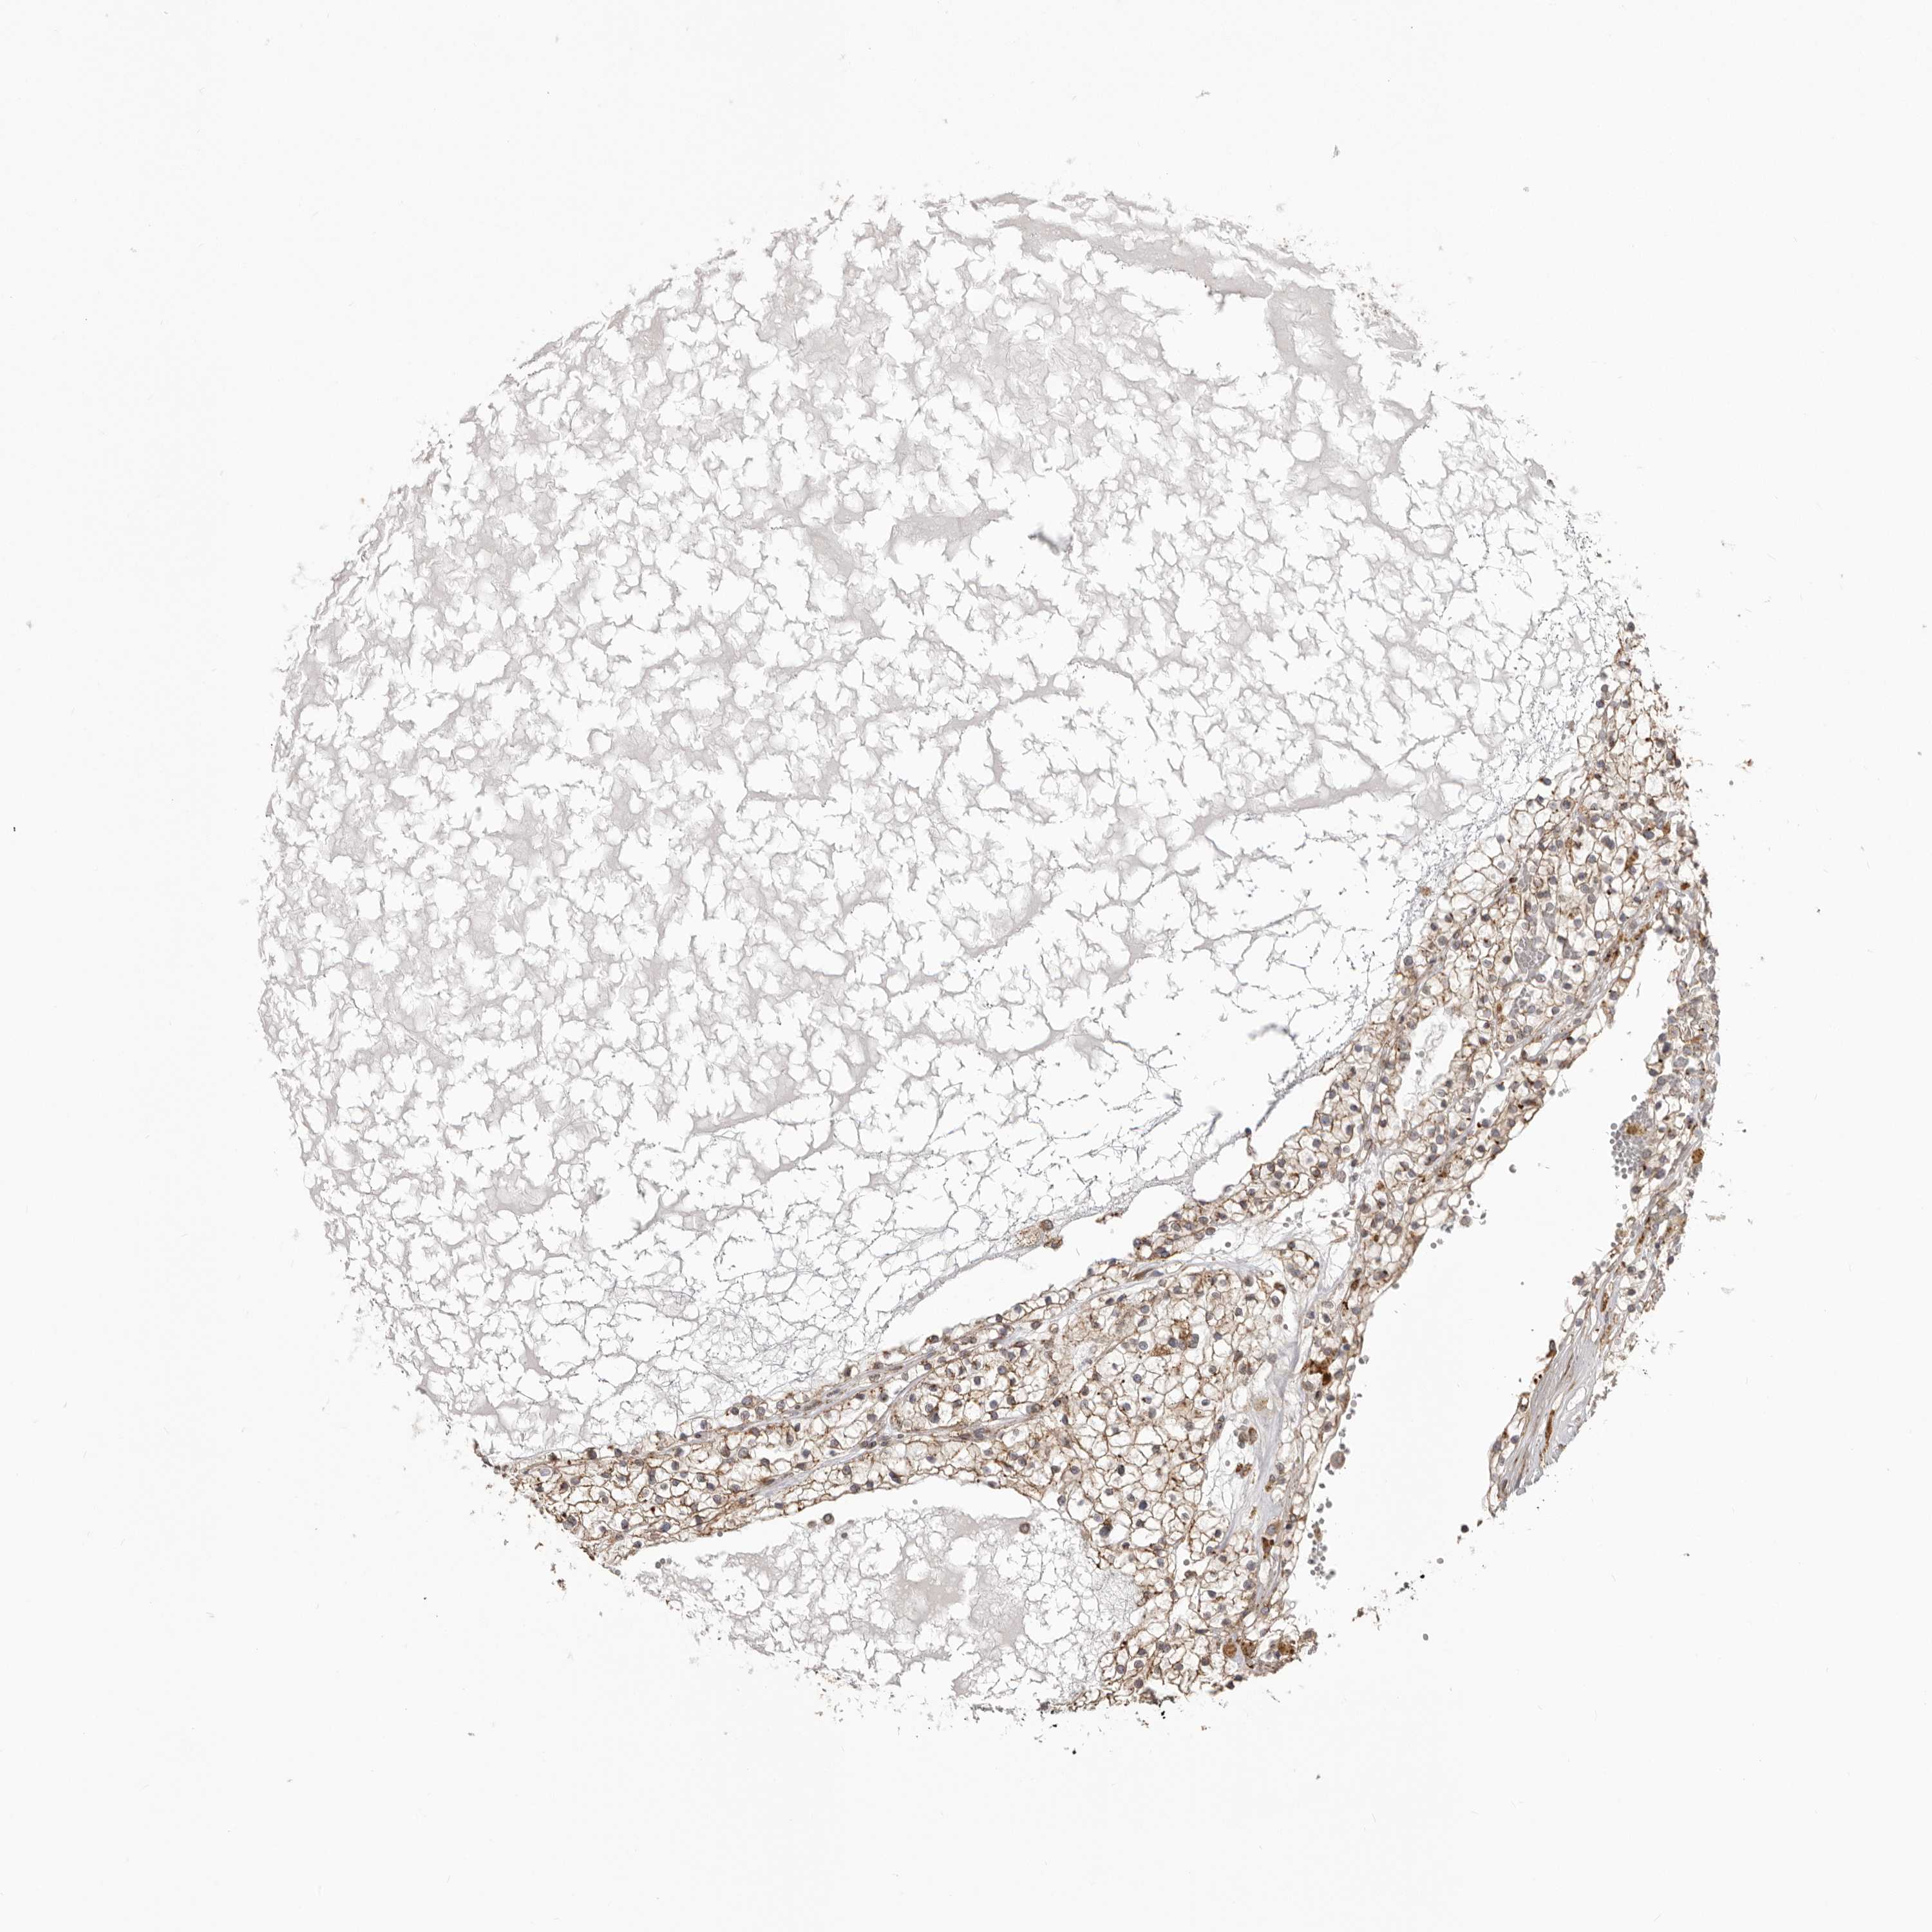

CANCER RENAL CANCER Show tissue menu

KICH TCGA KIRC TCGA KIRC VALIDATION KIRP TCGA PROTEIN RCC CPTAC PROTEIN EXPRESSION